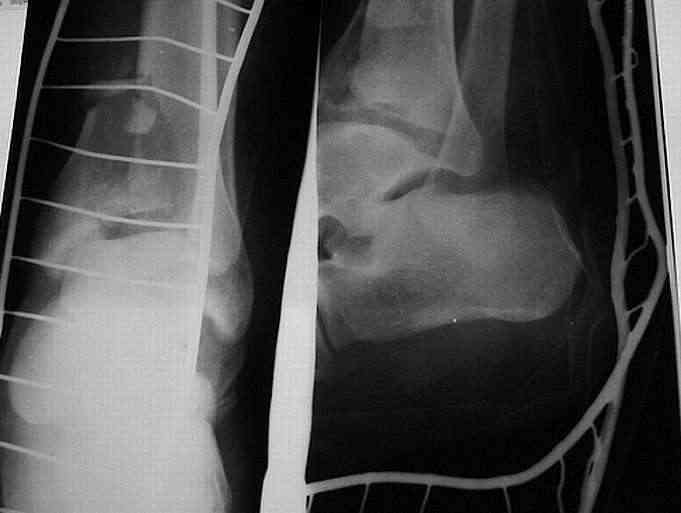

Здравствуйте, коллеги. Больной 26 лет, в 2004 году попал ко мне с диагнозом: синтезированный в аппарате Илизарова неполный внутрисуставной оскольчатый перелом дистального метафиза левой большеберцовой кости со смещением; выраженный остеопороз; множественное спицевое нагноение. Несостоятельность фиксации (костные отломки буквально "елозили" по спицам, несмотря на наличие упорных площадок).

Мной был демонтирован АВФ, удалены все спицы. Больной некоторое время лечился консервативно (шина Белера, антибиотики, перевязки). По заживлению и купировании гнойно-воспалительного процесса была произведена осткрытая репозиция, накостный остеосинтез 1/3 трубчатой пластиной. Такой вариант был принят из-за жуткого остеопороза и отказом больного от предложенного артродезирования голеностопного сустава сразу. Послеоперационный период без особенностей. Через год, больной пришел на осмотр на своих двоих, без дополнительной опоры, с жалобами на боли при ходьбе в обл. г/стопа и с желанием замкнуть сустав. В операционной столкнулся с неожиданной проблемой по удалению пластины, она была глубоко вмурована в толщу склерозированного метафиза на глубину 1.5 см; удалить не рискнул (считал, что металл помешает в ходе реконструкции и требуется его удаление).

Было решено, уже по ходу операции, выполнить артродез болтом-стяжкой, тем самым компрессируя резецированные суставные поверхности и смещая стопу латерально, дабы нивелировать варусную деформацию и восстанавливая тем самым опорную ось всей конечности.

Вчера (прошло около 8 месяцев)больной обратился ко мне в очередной раз с жалобами на боли умеренно-жгучего характера в области выстояния концов болта-стяжки. На момент осмотра: укорочение левой нижней конечности на 1,5 см; гипотрофия медиальной группы мышц голени и четырехглавой мышцы бедра; передвигается без дополнительной опоры в ортопедической обуви на растояние до 5 км; работает приемщиком цветных металлов (приходится перетаскивать грузы). На рентгенограмме, насколько это можно видеть, костного блока сформировать не удалось, но движений в голеностопном суставе нет - ни активных, ни пассивных. Послеоперационные рубцы б/о; свищей и нагноения не было. Активно больного наблюдать не приходилось, т.к. проживает в другом городе.

ЗЫ: Прошу прощения за очень низкое качество представленных ренгенограмм. Буду очень признателен за комментарии.